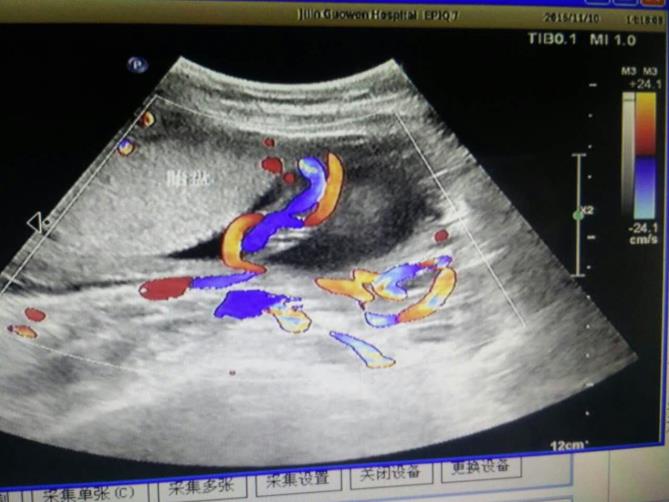

為該患常規(guī)檢查臍帶入口時發(fā)現(xiàn)臍帶入口位于胎盤下緣邊緣,胎兒超聲檢查無陽性發(fā)現(xiàn)。常規(guī)掃查右卵巢時,發(fā)現(xiàn)右卵巢旁可見腎臟回聲(正常情況下,右卵巢旁是不會掃查到腎臟回聲的),大小、形態(tài)如常,CDFI:腎內(nèi)血流灌注尚可,故囑患者左側(cè)臥位,顯示孕婦右腎位置、大小及形態(tài)正常,囑孕婦右側(cè)臥位,發(fā)現(xiàn)脾臟下方無腎臟回聲,故考慮該患左腎游走腎。該患于2016年12月2日復(fù)查,結(jié)果如前。